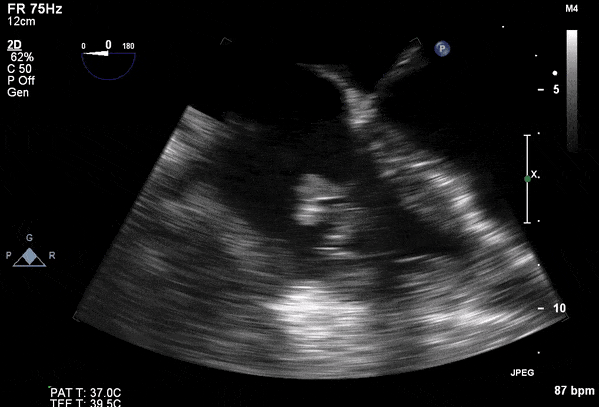

Role of Echocardiography

- Echo plays an important role in the diagnosis of infective endocarditis.

- Helps identify vegetations, new valvular lesions, abscess, and other complications of endocarditis.

- Transthoracic (TTE) should be performed in all cases of suspected infective endocarditis

- Transesophageal (TEE) should be performed if TTE images are inadequate or ongoing suspicion for infective endocarditis.

Transesophageal Images